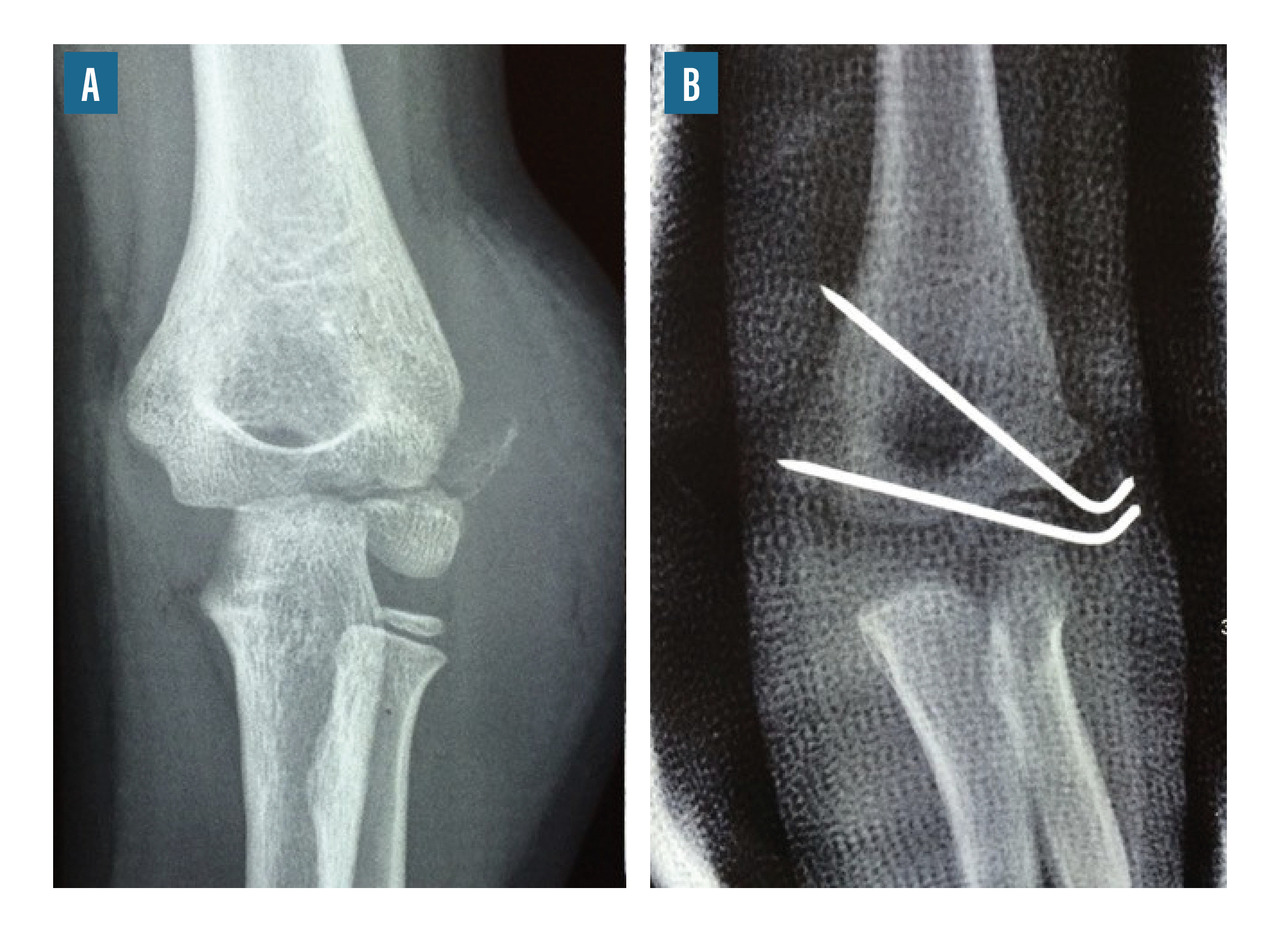

• le brochage direct (fig. 8) ;

• le vissage percutané par vis canulée montée sur des broches (fig. 9) ;

Le traitement chirurgical peut nécessiter un abord chirurgical, notamment dans les cas de fractures articulaires (fracture du condyle latéral, fractures intercondyliennes). Dans les autres cas, il s’agit habituellement de réductions orthopédiques maintenues par des broches ou un simple plâtre.